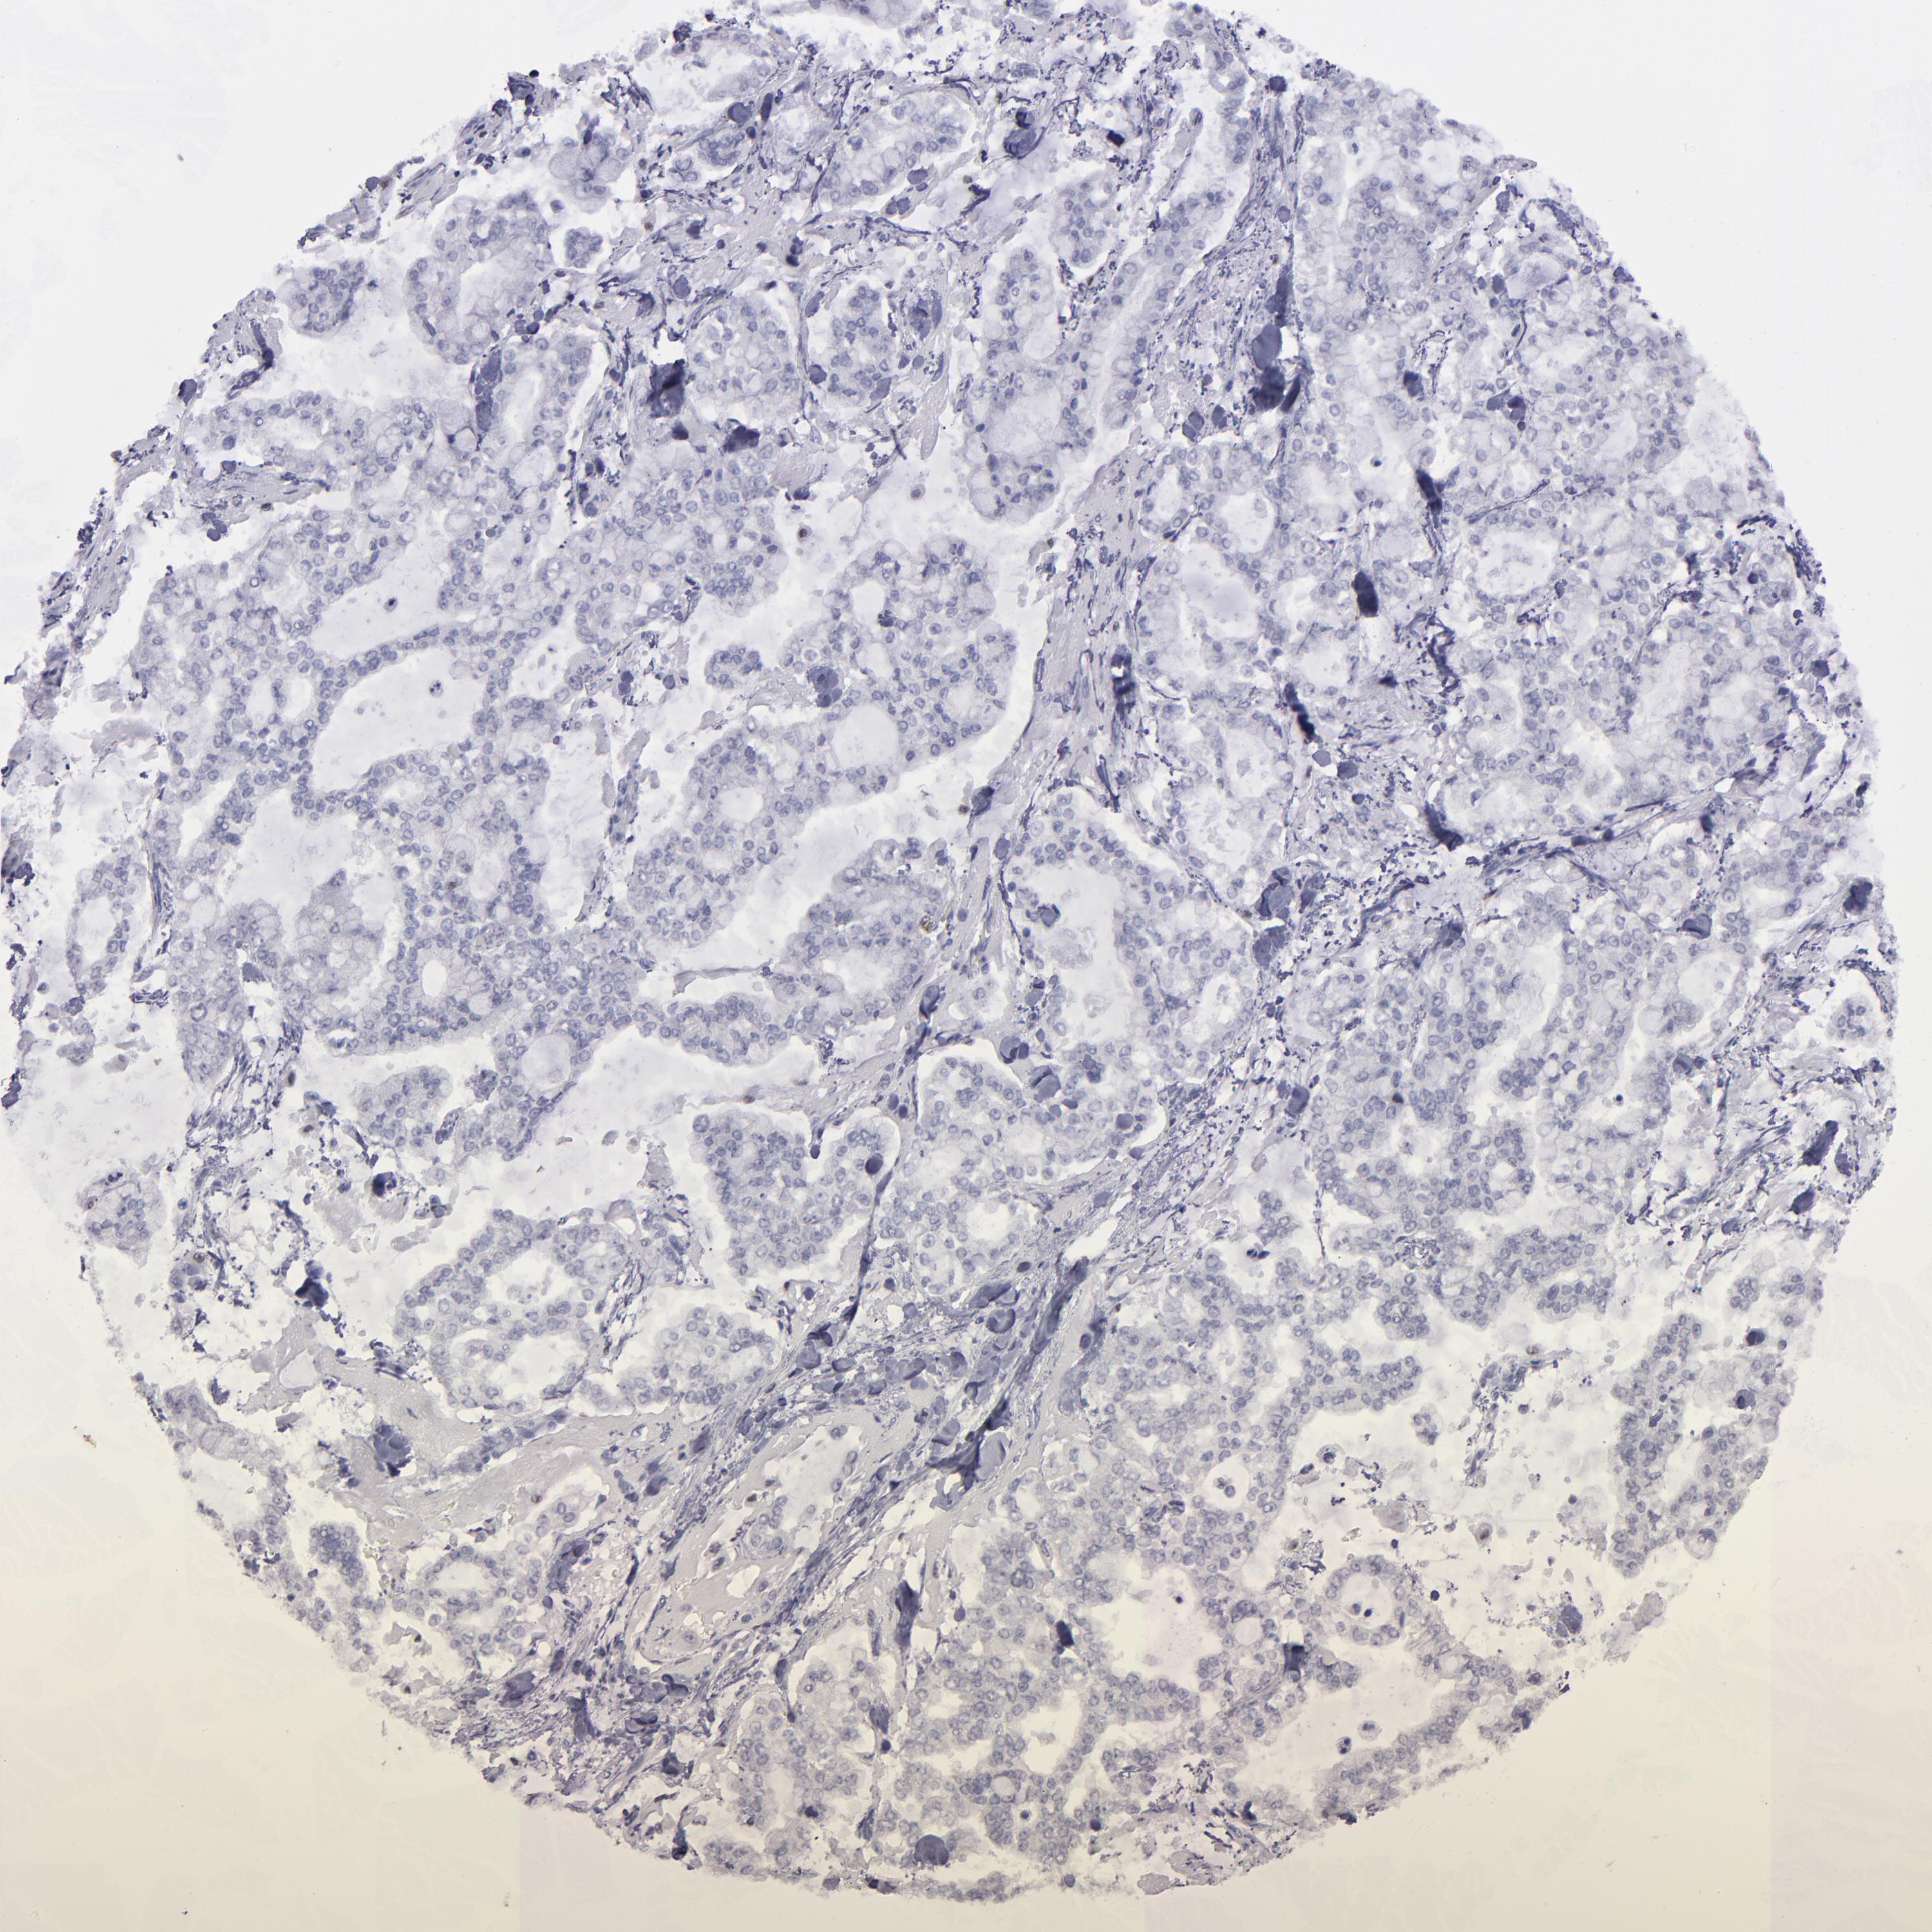

STOMACH CANCER - Protein expressioni

A mouse-over function shows sample information and annotation data. Click on an image to view it in a full screen mode. Samples can be filtered based on level of antibody staining by selecting one or several of the following categories: high, medium, low and not detected. The assay and annotation is described here.

Antibody stainingi

Antibody staining in the annotated cell types in the current human tissue is reported as not detected, low, medium, or high, based on conventional immunohistochemistry profiling in selected tissues. This score is based on the combination of the staining intensity and fraction of stained cells.

Each image is clickable and will lead to virtual microscopy that enables deeper exploration of all samples and also displays staining intensity scores, fraction scores and subcellular localization as well as patient and tissue information for each sample.

Antibody HPA002267

Antibody HPA002531

Antibody CAB013480

Staining

High

Medium

Low

Not detected

Intensity

Strong

Moderate

Weak

Negative

Quantity

>75%

75%-25%

<25%

None

Location

Nuclear

Cytoplasmic/membranous

Cytoplasmic/membranous,nuclear

Adenocarcinoma, NOS

Adenocarcinoma, High grade